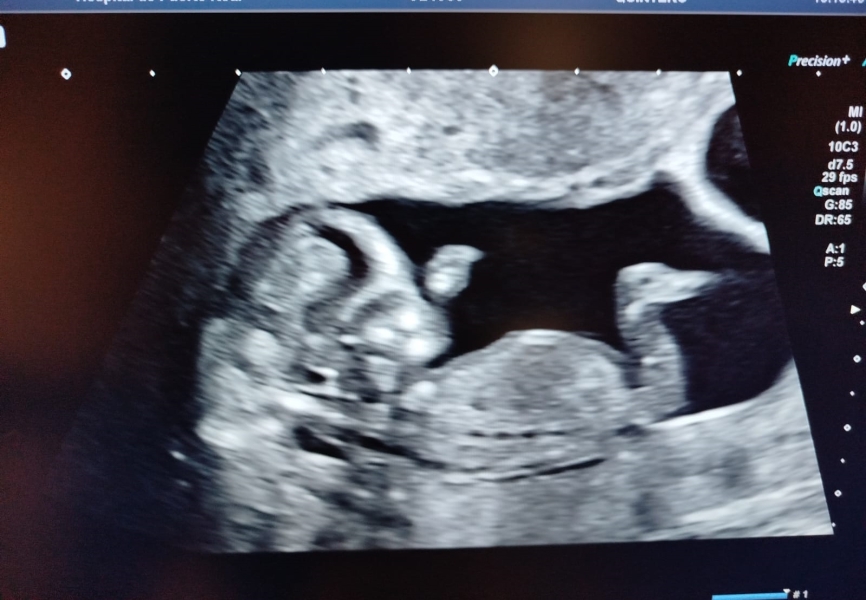

Hi all! Sorry I´ve been away from mumsnet for a while. I´ve been really busy lately and also everytime I thought about reading the thread I couldn´t shake the feeling that I was making everything up. Sometimes I can´t believe it´s happening buuuuut....

I had another scan today and saw the babies and for today it all seems real again 😂I will post the pictures (hope the site allows me to do it).

They all are in different sacs with individual placentas. All seems well.

OMG! It's triplets!!!